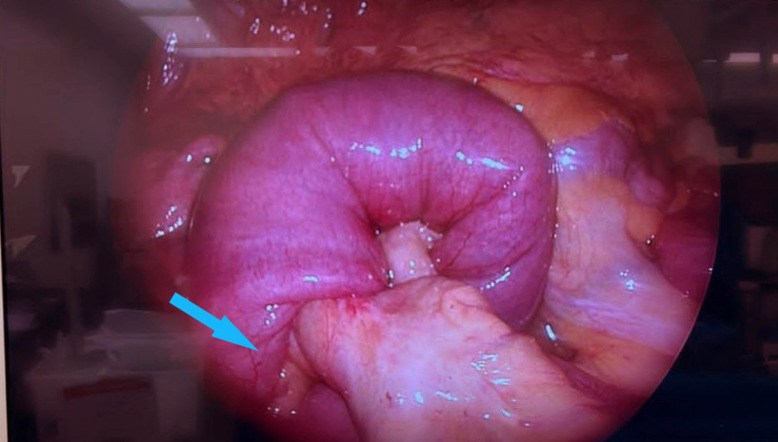

This patient reported severe persistent abdominal pain requiring multiple doses of analgesia and fluid resuscitation. The surgical team were consulted in ED who assessed the patient and reviewed all investigations including CT images of abdomen and pelvis. In view of the patient’s clinical condition in conjunction with the imaging reports, a decision was made to proceed for operative management. The patient underwent an urgent diagnostic laparoscopy. This confirmed the preoperative diagnosis of jejunojejunal intussusception located approximately 250 cm from the terminal ileium (figure 3). A small bowel resection containing the jejunojejunal intussusception segment was performed and a primary anastomosis fashioned. The immediate postoperative period was uneventful and the patient was treated with intravenous fluids and antibiotics. The patient was discharged from hospital after 3 days.

Intussusception segment on diagnostic laparoscopy showing bowel (blue arrow) telescoping into a contiguous segment of bowel.